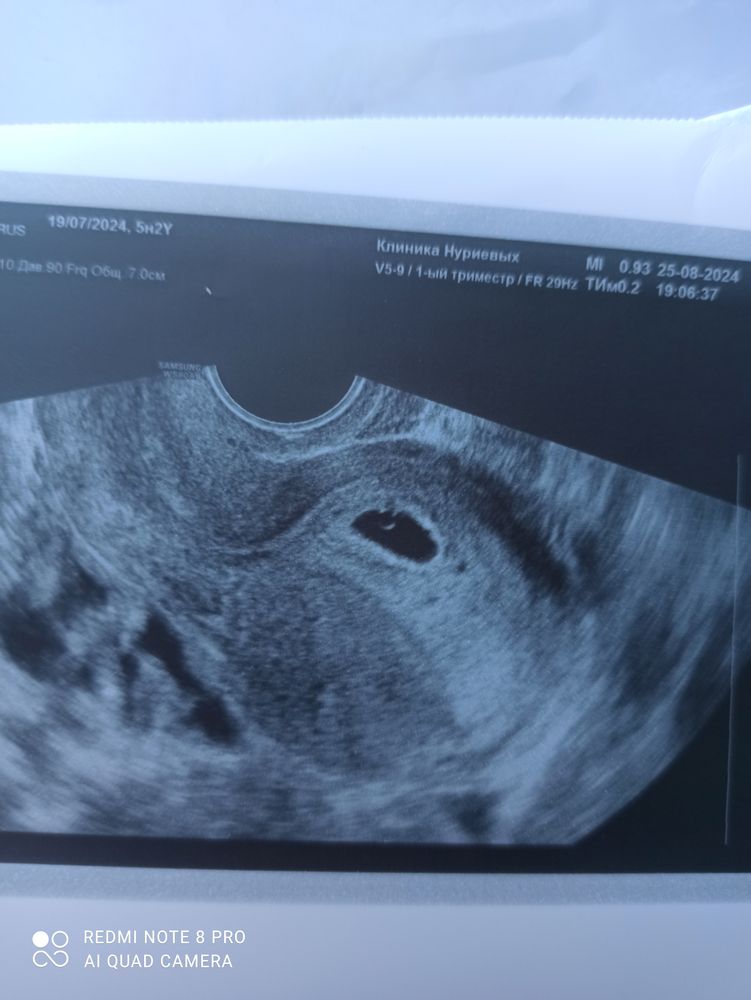

Подскажите, пожалуйста, на снимке виднеется эмбрион?

Хорошо виден желточный мешок, его наличие говорит о нормальной беременности. Можете сходить через недельку на узи и уже увидите эмбрион и сб.

Это на жм похоже Эмбрион через 5-7 дней можно проверить на контрольном узи

Скорее это желточный мешок. А эмбрион будет чуть позже

Нет, ЖМ